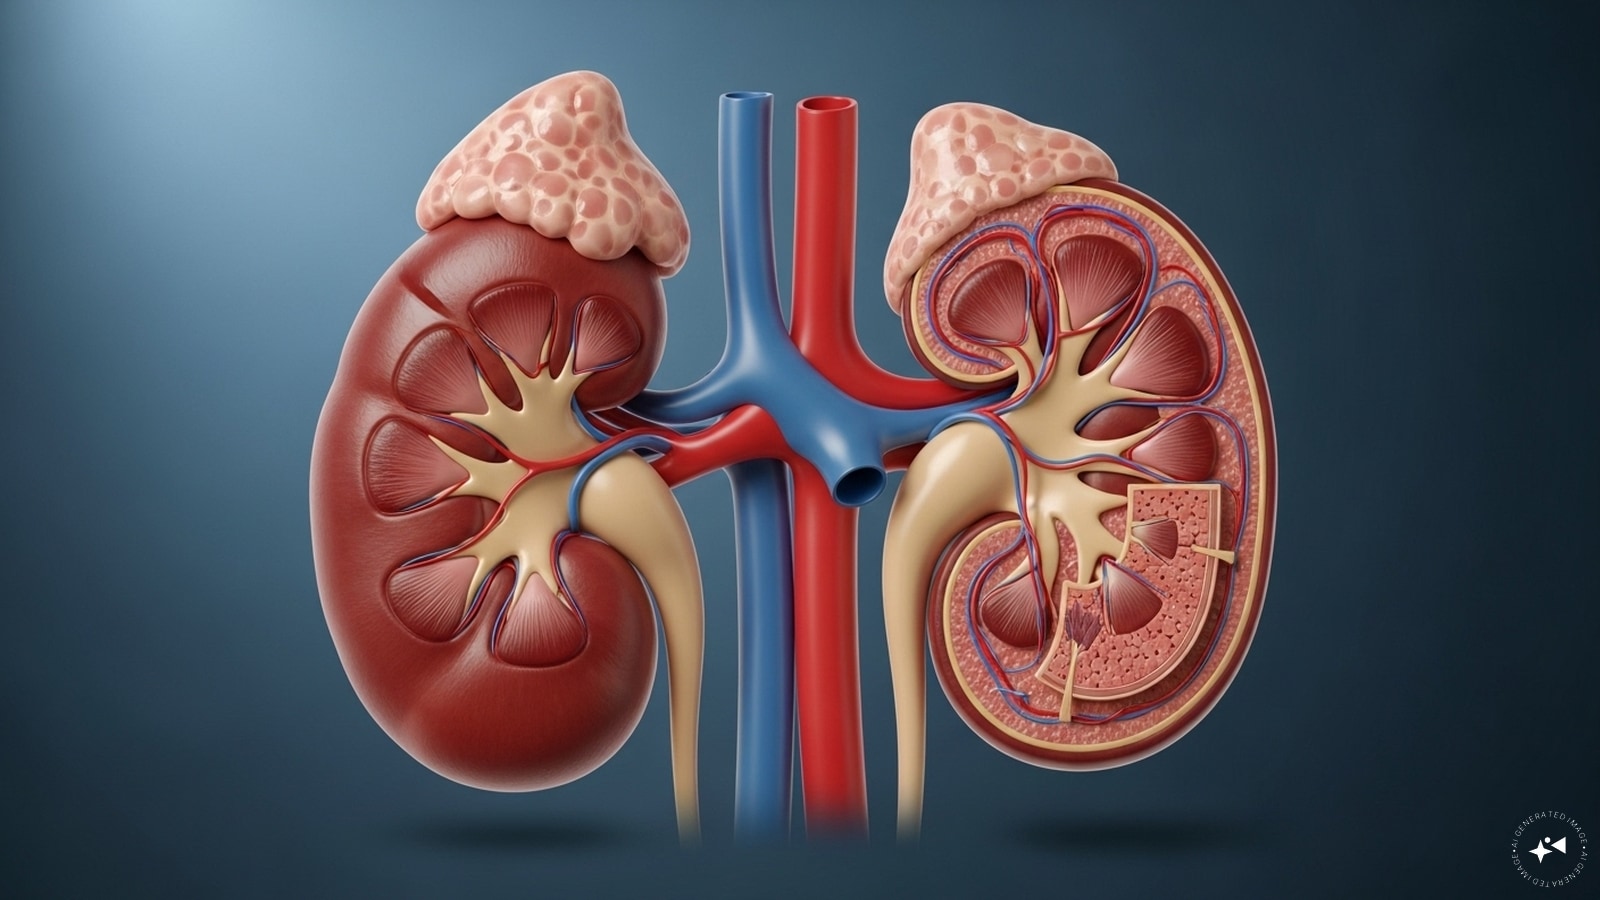

Your kidneys quietly filter blood and remove waste every day. When they struggle, the warning signs are often subtle—catching them early is key.

Unexplained Swelling: Puffiness around ankles, feet, or face may signal kidneys leaking protein. Without enough protein in the blood, fluids build up in tissues.

Foamy or Bubbly Urine: Persistent frothy urine can mean excess protein (proteinuria) is being lost. It’s an early red flag that kidney filters are breaking down.

Sudden Weight Gain: A quick rise on the scale without lifestyle changes could be fluid retention. This “heavy” weight often comes with swelling and sluggishness.

Persistent Fatigue: Protein loss and toxin build-up reduce energy levels. This isn’t normal tiredness—it’s deep exhaustion that doesn’t improve with rest.

Appetite Loss & Nausea: As kidneys fail to filter properly, toxins accumulate. This makes food less appealing, sometimes triggering nausea or vomiting.

Frequent Nighttime Urination: A strong urge to urinate at night (nocturia) signals kidneys struggling to balance fluids. It disrupts sleep and points to early strain.

Frequent Infections: Weakened immunity from protein loss leaves the body prone to UTIs and respiratory infections that take longer to heal.

Chronic kidney disease affects 10% of the global population. If you notice these signs, consult a doctor early.